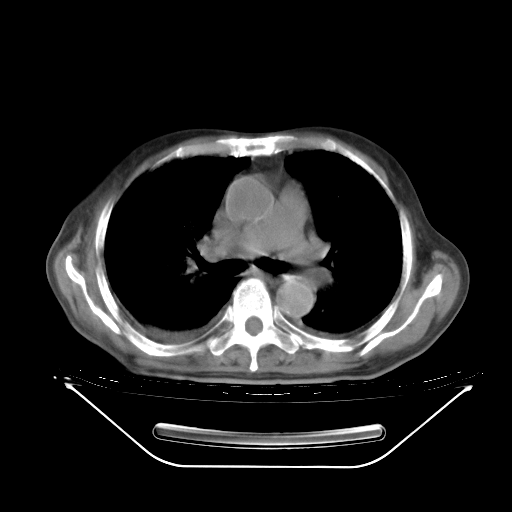

今天复查肺部CT,发现双肺广泛磨玻璃样改变。所以我把3月19日和5月9日相隔50天的肺部CT上传。请大家会诊。

5月9日肺部CT(在4月27日齐鲁医院肺部CT描述部分肺组织磨玻璃样改变,12天后肺组织广泛磨玻璃样改变)

大致读了系列胸部CT:纵隔窗无明显异常,肺窗:从4、27至今:主要是双肺中下野外带可见毛玻璃样改变,目前处于急性肺泡炎阶段,至于原因考虑1、结替组织或胶原血管性疾病所致?2、恶性疾病如恶组在肺部所致的表现或细支气管肺泡癌?3、药物或其它原因如肺蛋白沉着症所致肺泡炎目前不太可能?总之,明天就去请我院的呼吸科、感染科、血液科和临免专家会诊哈。